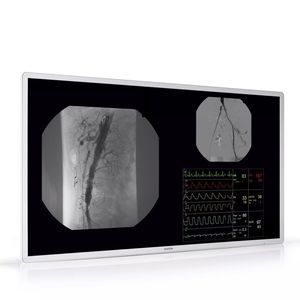

Medizinischer Full-HD-21,5-Zoll-Touchscreen

Der AMM 215WTTP ist ein 21,5-Zoll-Touchscreen, der für medizinische Fachkräfte entwickelt wurde, die eine präzise und zuverlässige Interaktion mit der Touch-Benutzeroberfläche benötigen.

Ergonomische Interaktion

Der AMM 215WTTP ist für mehr Ergonomie entwickelt worden. Der 21,5-Zoll-Bildschirm ist einfach zu bedienen und verfügt über die perfekte Größe und das perfekte Format für eine Vielzahl von Anwendungen, einschließlich digitalen OPs und Medizinwagen. Dank seiner Full-HD-Auflösung hat das klinische Personal Zugang zu umfassenden Detailinformationen.

Das Display verfügt über die Technologie Projected Capacitive Touch mit Multi- und Single-Touch-Funktionalität. Es ermöglicht den klinischen Personal auch beim Tragen von Handschuhen problemlos mit der Benutzeroberfläche auf dem Monitor zu interagieren.

ür medizinische Umgebungen entwickelt

Der AMM 215WTTP ist medizinisch zertifiziert und für den Einsatz in einer anspruchsvollen, erfolgskritischen Umgebung wie dem OP-Raum geeignet. Das rahmenlose Design ermöglicht einfache Reinigung und Desinfektion, eine wesentliche Voraussetzung für alle chirurgischen und klinischen Umgebungen.